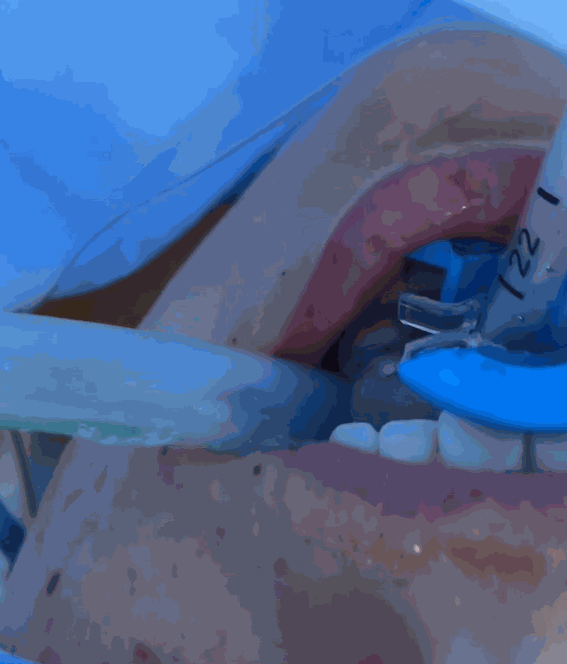

Facilidad de colocación e higiene

El dispositivo se introduce fácilmente en la cavidad oral una vez el paciente ha sido entubado y con una leve presión el tubo queda fijado al clip. Facilita su extracción el no tener que maniobrar con nudos ni despegar adhesivos.

Garantiza espacio de acceso

Permite el fácil acceso a la cavidad bucal para mantenimiento e higiene sin tener que retirar el dispositivo.

Permite desplazar el dispositivo

¡Sin uso de cintas adhesivas o bandas para la cabeza!

No es agresivo con la cara, piel y cabeza y permite un cuidado e higiene adecuados para el paciente.